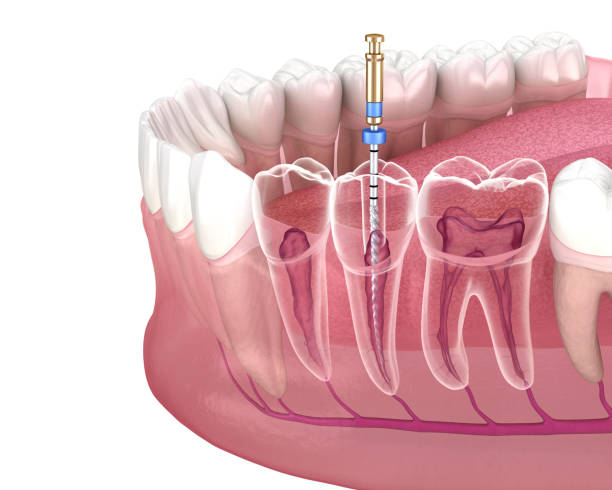

根管治療のイラスト

根管治療の目的

虫歯の進行が進んでしまって痛みが出ているケースやさらに細菌が歯の奥まで進行し、歯根の先に膿が溜まってしまっている状況などでは、根管治療がどうしても必要になってきます。